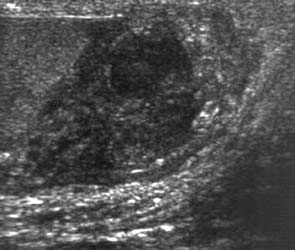

Ultrasound

What is ultrasound?

Ultrasound is a technique which uses sound waves of high frequency to produce

images.

How does ultrasound work?

Different parts in the body have a different response to high-frequency

ultrasonic waves passed through them. When ultrasound waves are passed through

the body, many tissues reflect sound waves partially and transmit the rest,

which are then reflected back from deeper structures. The reflected waves are

measured and depending on the time it takes for them to return, the depth of the

echo is decided - the intensity decides the grayness of the area

Where is ultrasound useful?

Ultrasound is used in many parts of the body, specifically to look at the fetus,

for other gynecological abnormalities and to look at the abdomen, orbits,

thyroid gland, breast, testes, etc.